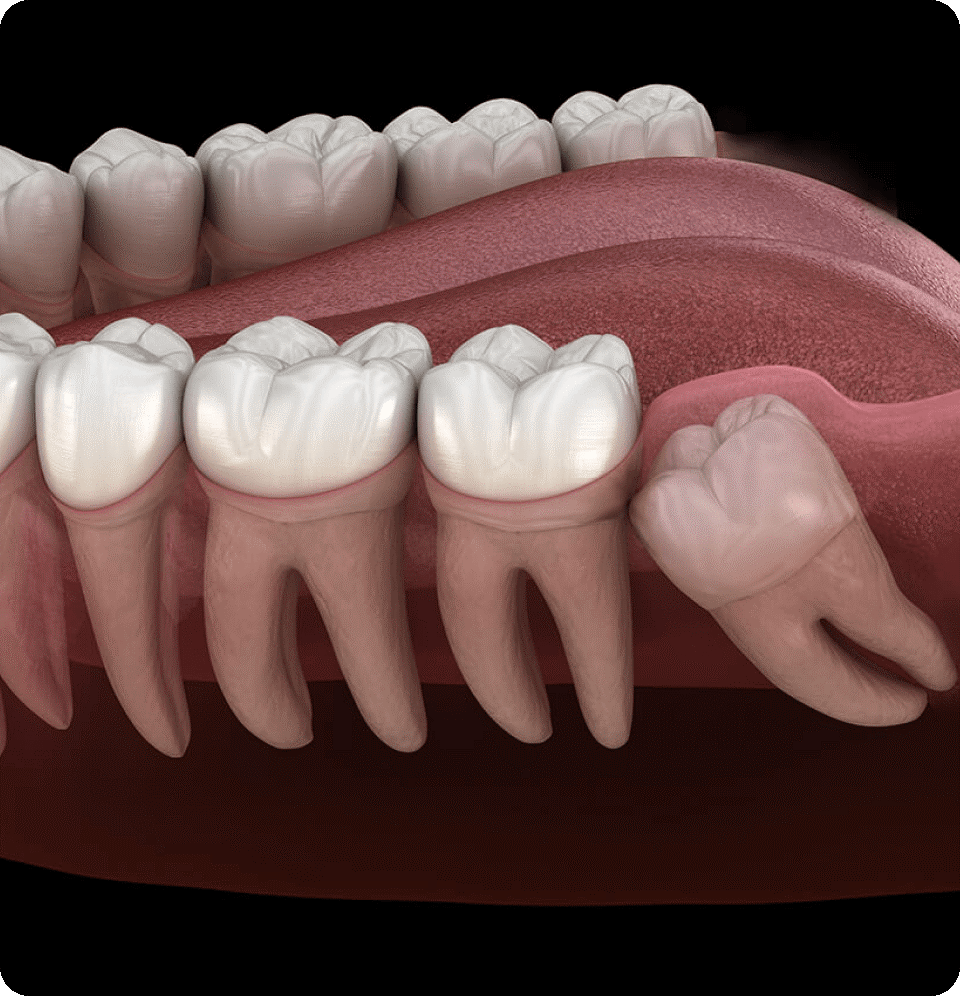

- Impacted teeth

- Wisdom Tooth Extraction